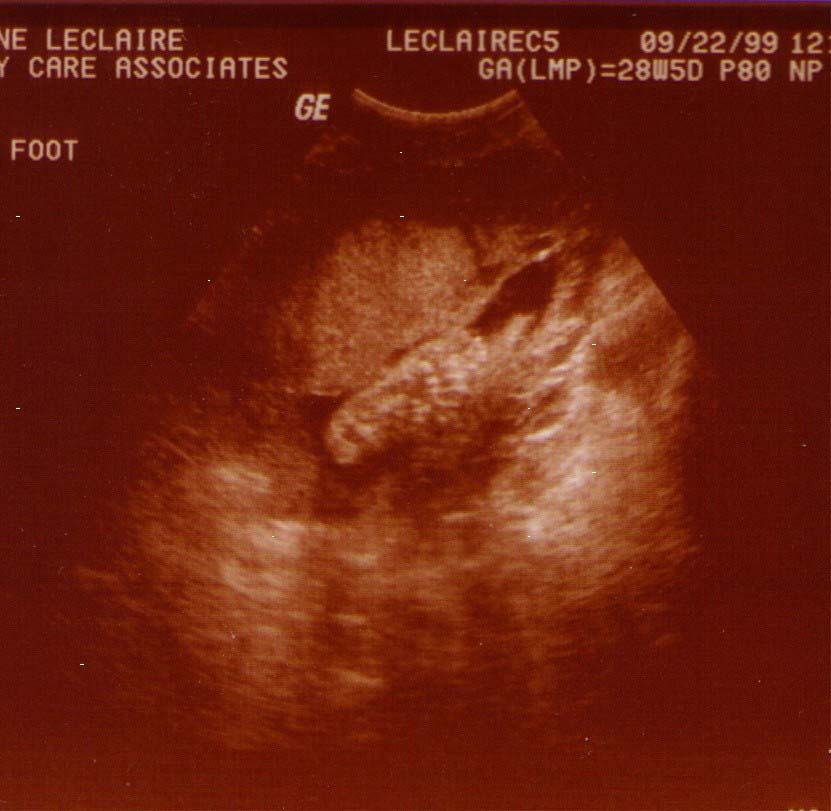

The Gender picture was right he's a boy!